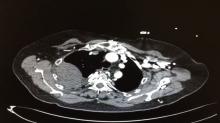

In the ER, the patient had a 220/115 arterial blood pressure, 5.6 INR, 20000 WBC, 2500 D-Dimer, and an unremarkable ECG. Her chest x-ray revealed massive pleural effusion, and a CT scan was done to rule out dissection of the aorta. The CT scan revealed a large extrapleural hematoma, and it was suspected that there was bleeding from the intercostal arteries. The patient was admitted to the cardiothoracic ICU department, and was treated with FFP and antihypertensive drugs. The next day, after the correction of the INR, she underwent a uniportal VATS surgery to evacuate the hematoma. The patient was discharged home on the third post-operative day.